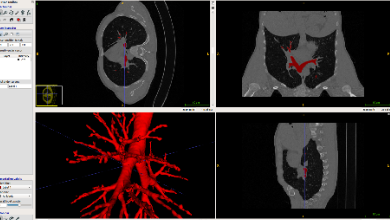

健培科技與德國(guó)KanMedIm推進(jìn)腹部微創(chuàng)手術(shù)AI導(dǎo)航的研發(fā)合作